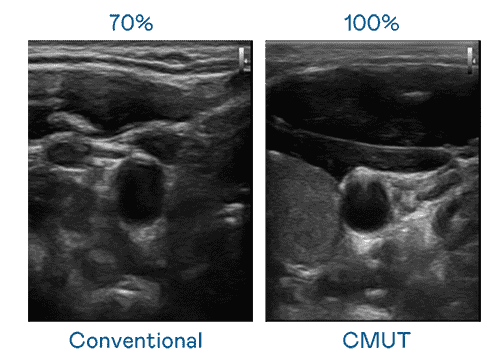

CMUT 技术是一种用电容式微机电元件来产生超音波讯号的技术。。。与传统 PZT 压电式技术相比,,CMUT 频宽增加 30%,,更宽频的超音波讯号让影像解析度大幅提升,,,,是实现高影像品质医疗超音波扫描、、、、促进精准医疗发展的关键技术。。。

大频宽带来超清晰影像

超音波影像的解析度高低,,,首先取决于探头能发出的讯号频宽。。。。银河集团 CMUT 可提供高清晰的超音波讯号,,,提供高频宽、、、高灵敏度、、、影像纹理细节更高的超音波影像,,,,协助医护人员缩短影像判读时间及利用精准的医疗影像进行诊断。。。。